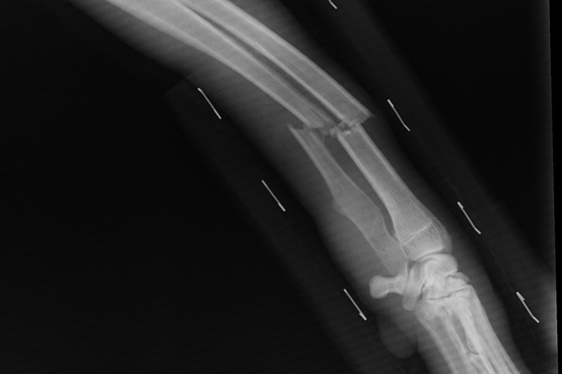

• Średni uszczerbek (art. 157 § 1 k.k.) – np. złamanie kości, obrażenia powodujące rozstrój zdrowia trwający powyżej 7 dni.